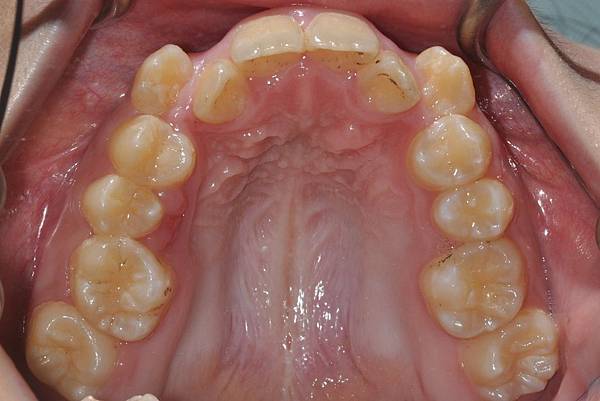

拔牙改善高位虎牙

虎牙妹的女神蛻變之旅~

此案例因為空間不足排列牙齒,

考量到不拔牙將使得牙齒前凸破壞患者原本和諧的側臉。

故上下左右各拔一小臼齒。